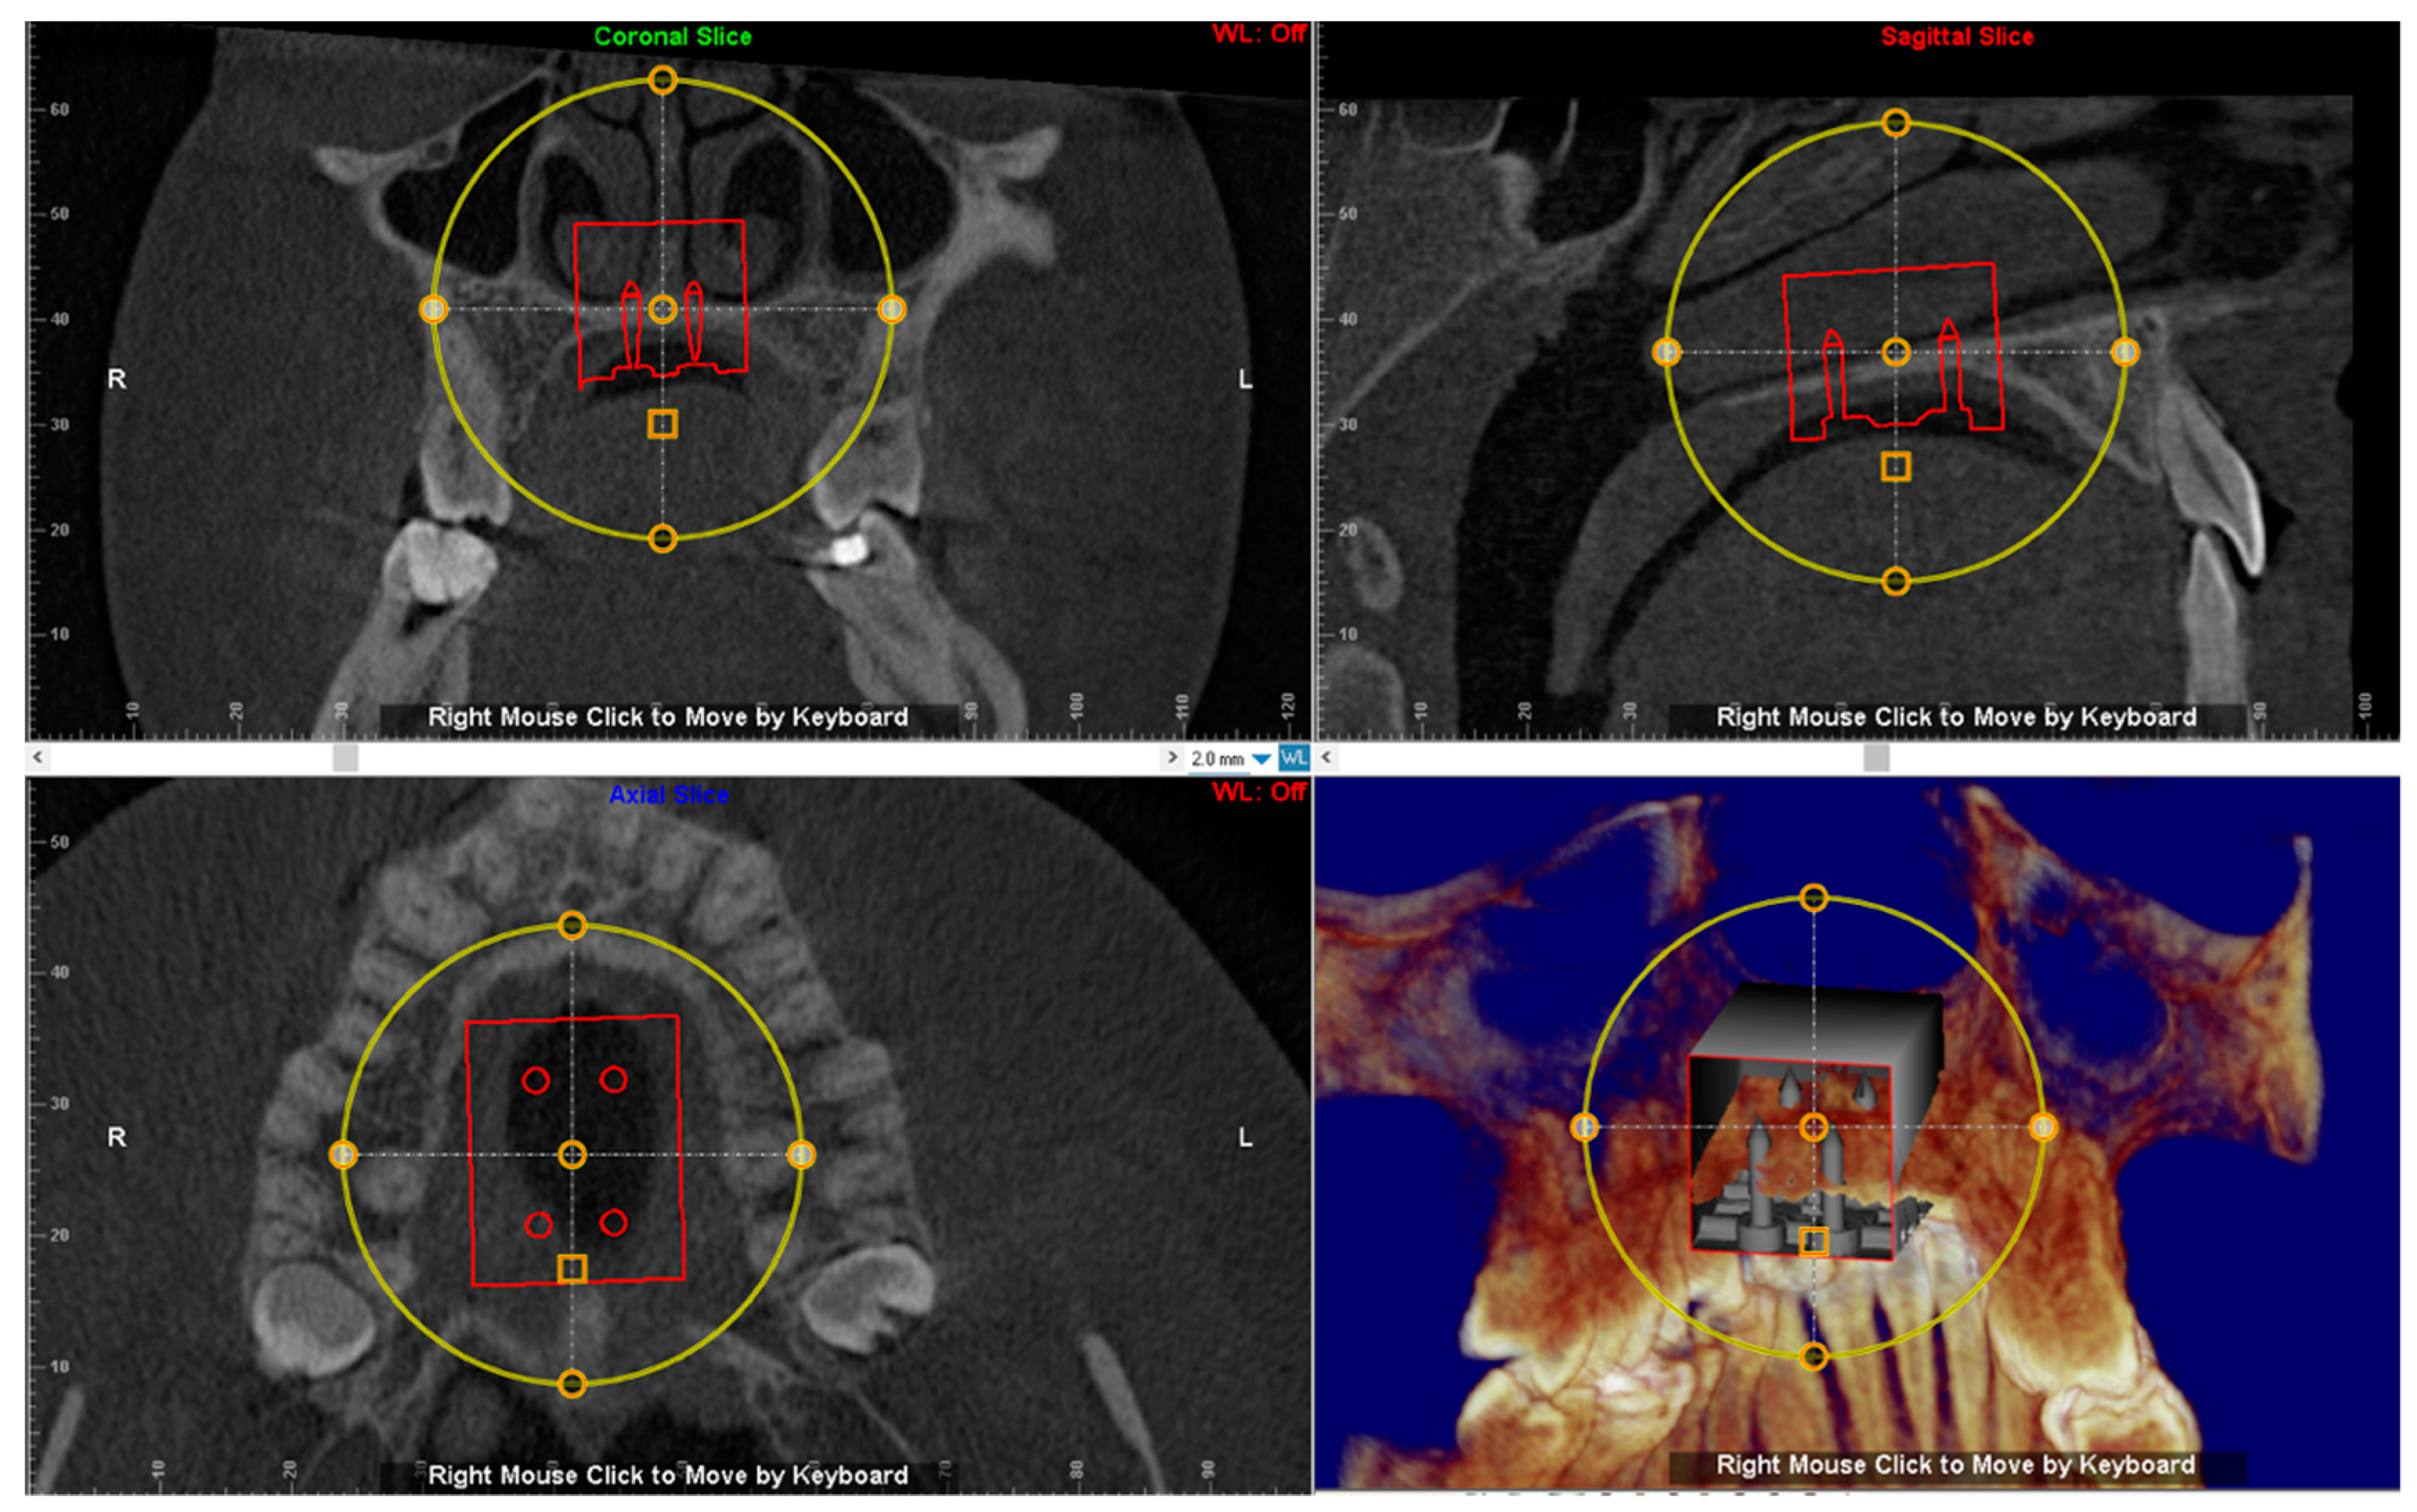

The digital model of maxillary arch is superimposed onto the CBCT DICOM file by selecting specific landmarks along the dental arch in both files (points-based registration), which allows identification of the most suitable vertical and anteroposterior placement of the MSE according to the following goals: bicortical insertion of the miniscrews, close proximity of the lower base of the MSE to the palatal mucosa and central placement of the screw using the nasal septum as visual reference (Figure 4). All these parameters were evaluated in sagittal, coronal, and axial views, and the position of the negative template of MSE was adjusted according to these parameters (Figure 5).

Figure 4.

Superimposition of the digital model of maxillary arch onto the DICOM file for identification of the most suitable vertical and anteroposterior placement of the MSE.

Figure 5.

The position of the negative template of MSE is determined in sagittal, coronal and axial views. See the design of the expander with the four miniscrews that are engaged in the cortical bone of the palate and nasal floor.